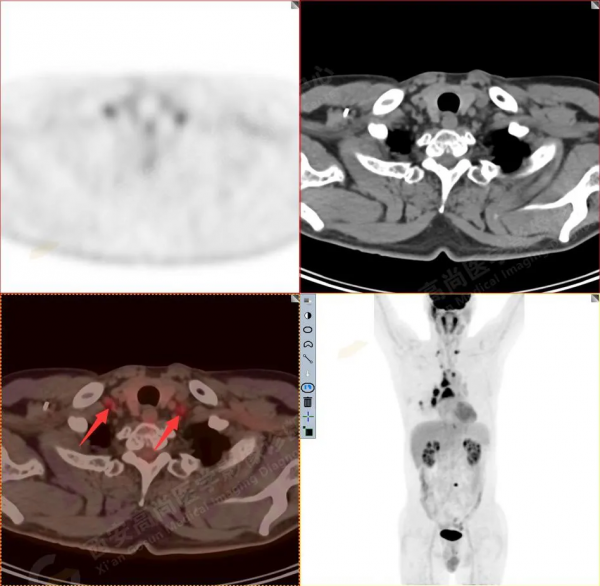

2.以下為部分全身多發轉移灶

3.右側頸部(Ⅱ-Ⅴ區)、右側腋窩區、右側肺門及縱隔(1R、1L、2、4、6、7組)、肝門區多發腫大淋巴結,呈不同程度異常增高,均考慮為淋巴結轉移。

4.肝S4、8段團塊狀及結節狀低密度病變,以S4段病變為著,呈不同程度FDG代謝異常增高,考慮為肝多發轉移。

5.右側肱骨上段、左側肩胛骨、右側鎖骨胸骨端、胸骨、雙側多發肋骨、脊柱多發椎體及附件、雙側髂骨、雙側髖臼、雙側恥骨、雙側肱骨上段多發成骨性病變,呈不同程度FDG代謝異常增高,考慮為多發骨轉移瘤。